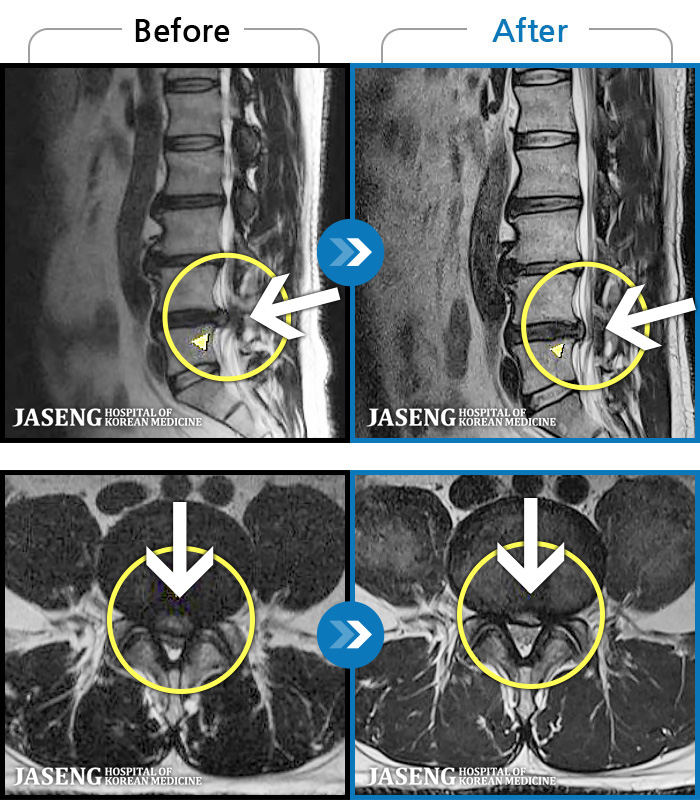

- MRI ġ

MRI ġ

97 MRI ũ ʸ Ȯϼ.

[_㸮ũ] ð ɰų, Ͼ ݺ ߳ Į ° ־ϴ.